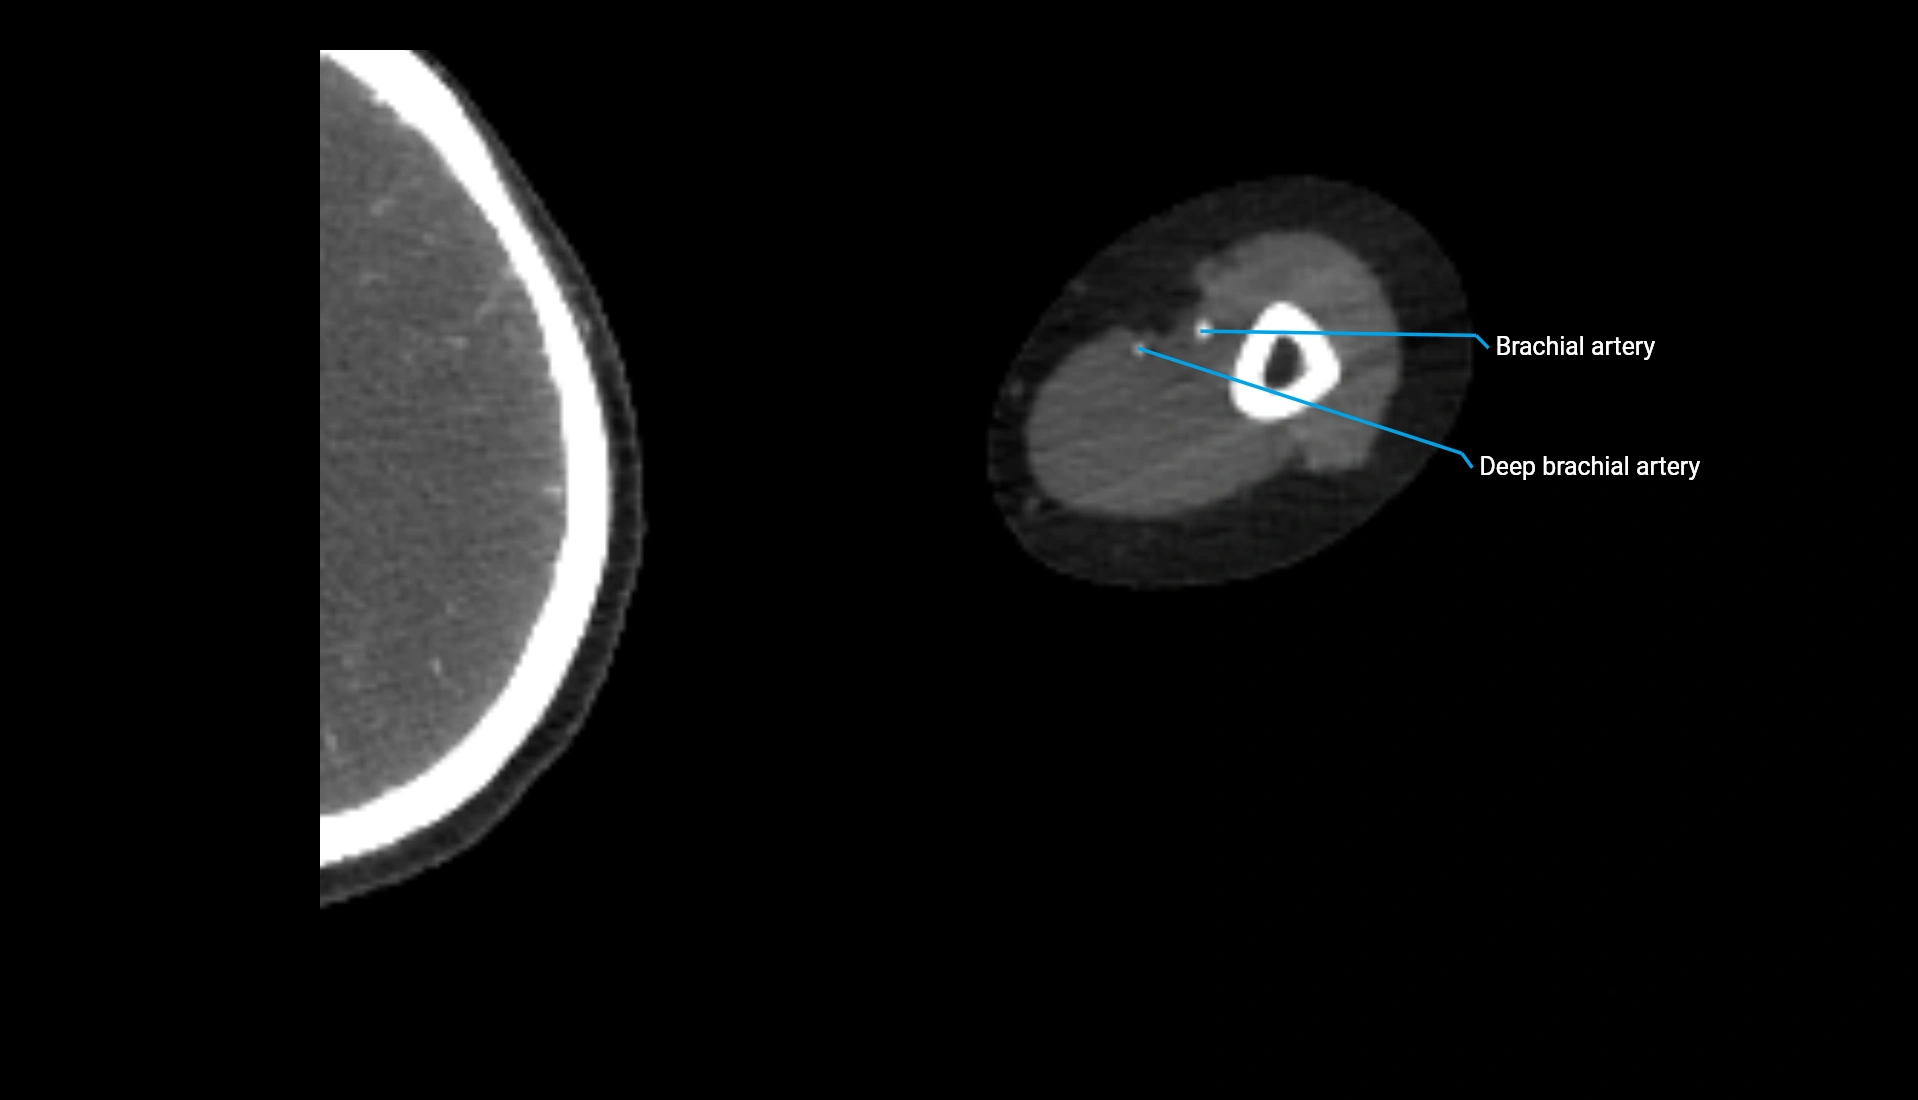

CT Appearance

Non-Contrast CT:

• Cortex: High-density, sharply defined

• Subchondral bone: Dense cancellous matrix

• Articular surface: Smooth concave contour articulating with the capitellum

• Excellent for evaluating bone integrity, alignment, and subtle fractures